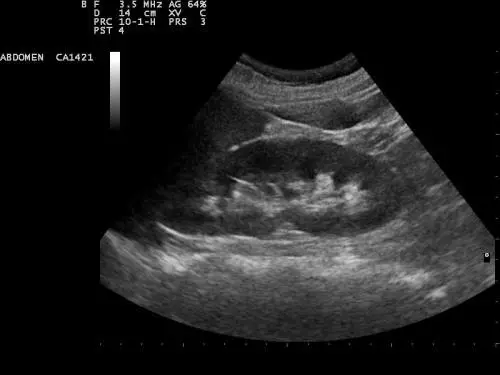

L’ecografia è uno strumento diagnostico efficace per prevenire il tumore al rene. È una malattia subdola i cui sintomi sono spesso sottovalutati dai pazienti. Colpisce maggiormente gli uomini

Questa metodologia diagnostica, come afferma l'urologo Pierfrancesco Bassi, può rivelarsi fondamentale per scoprire carcinomi renali piccoli e dunque curabili